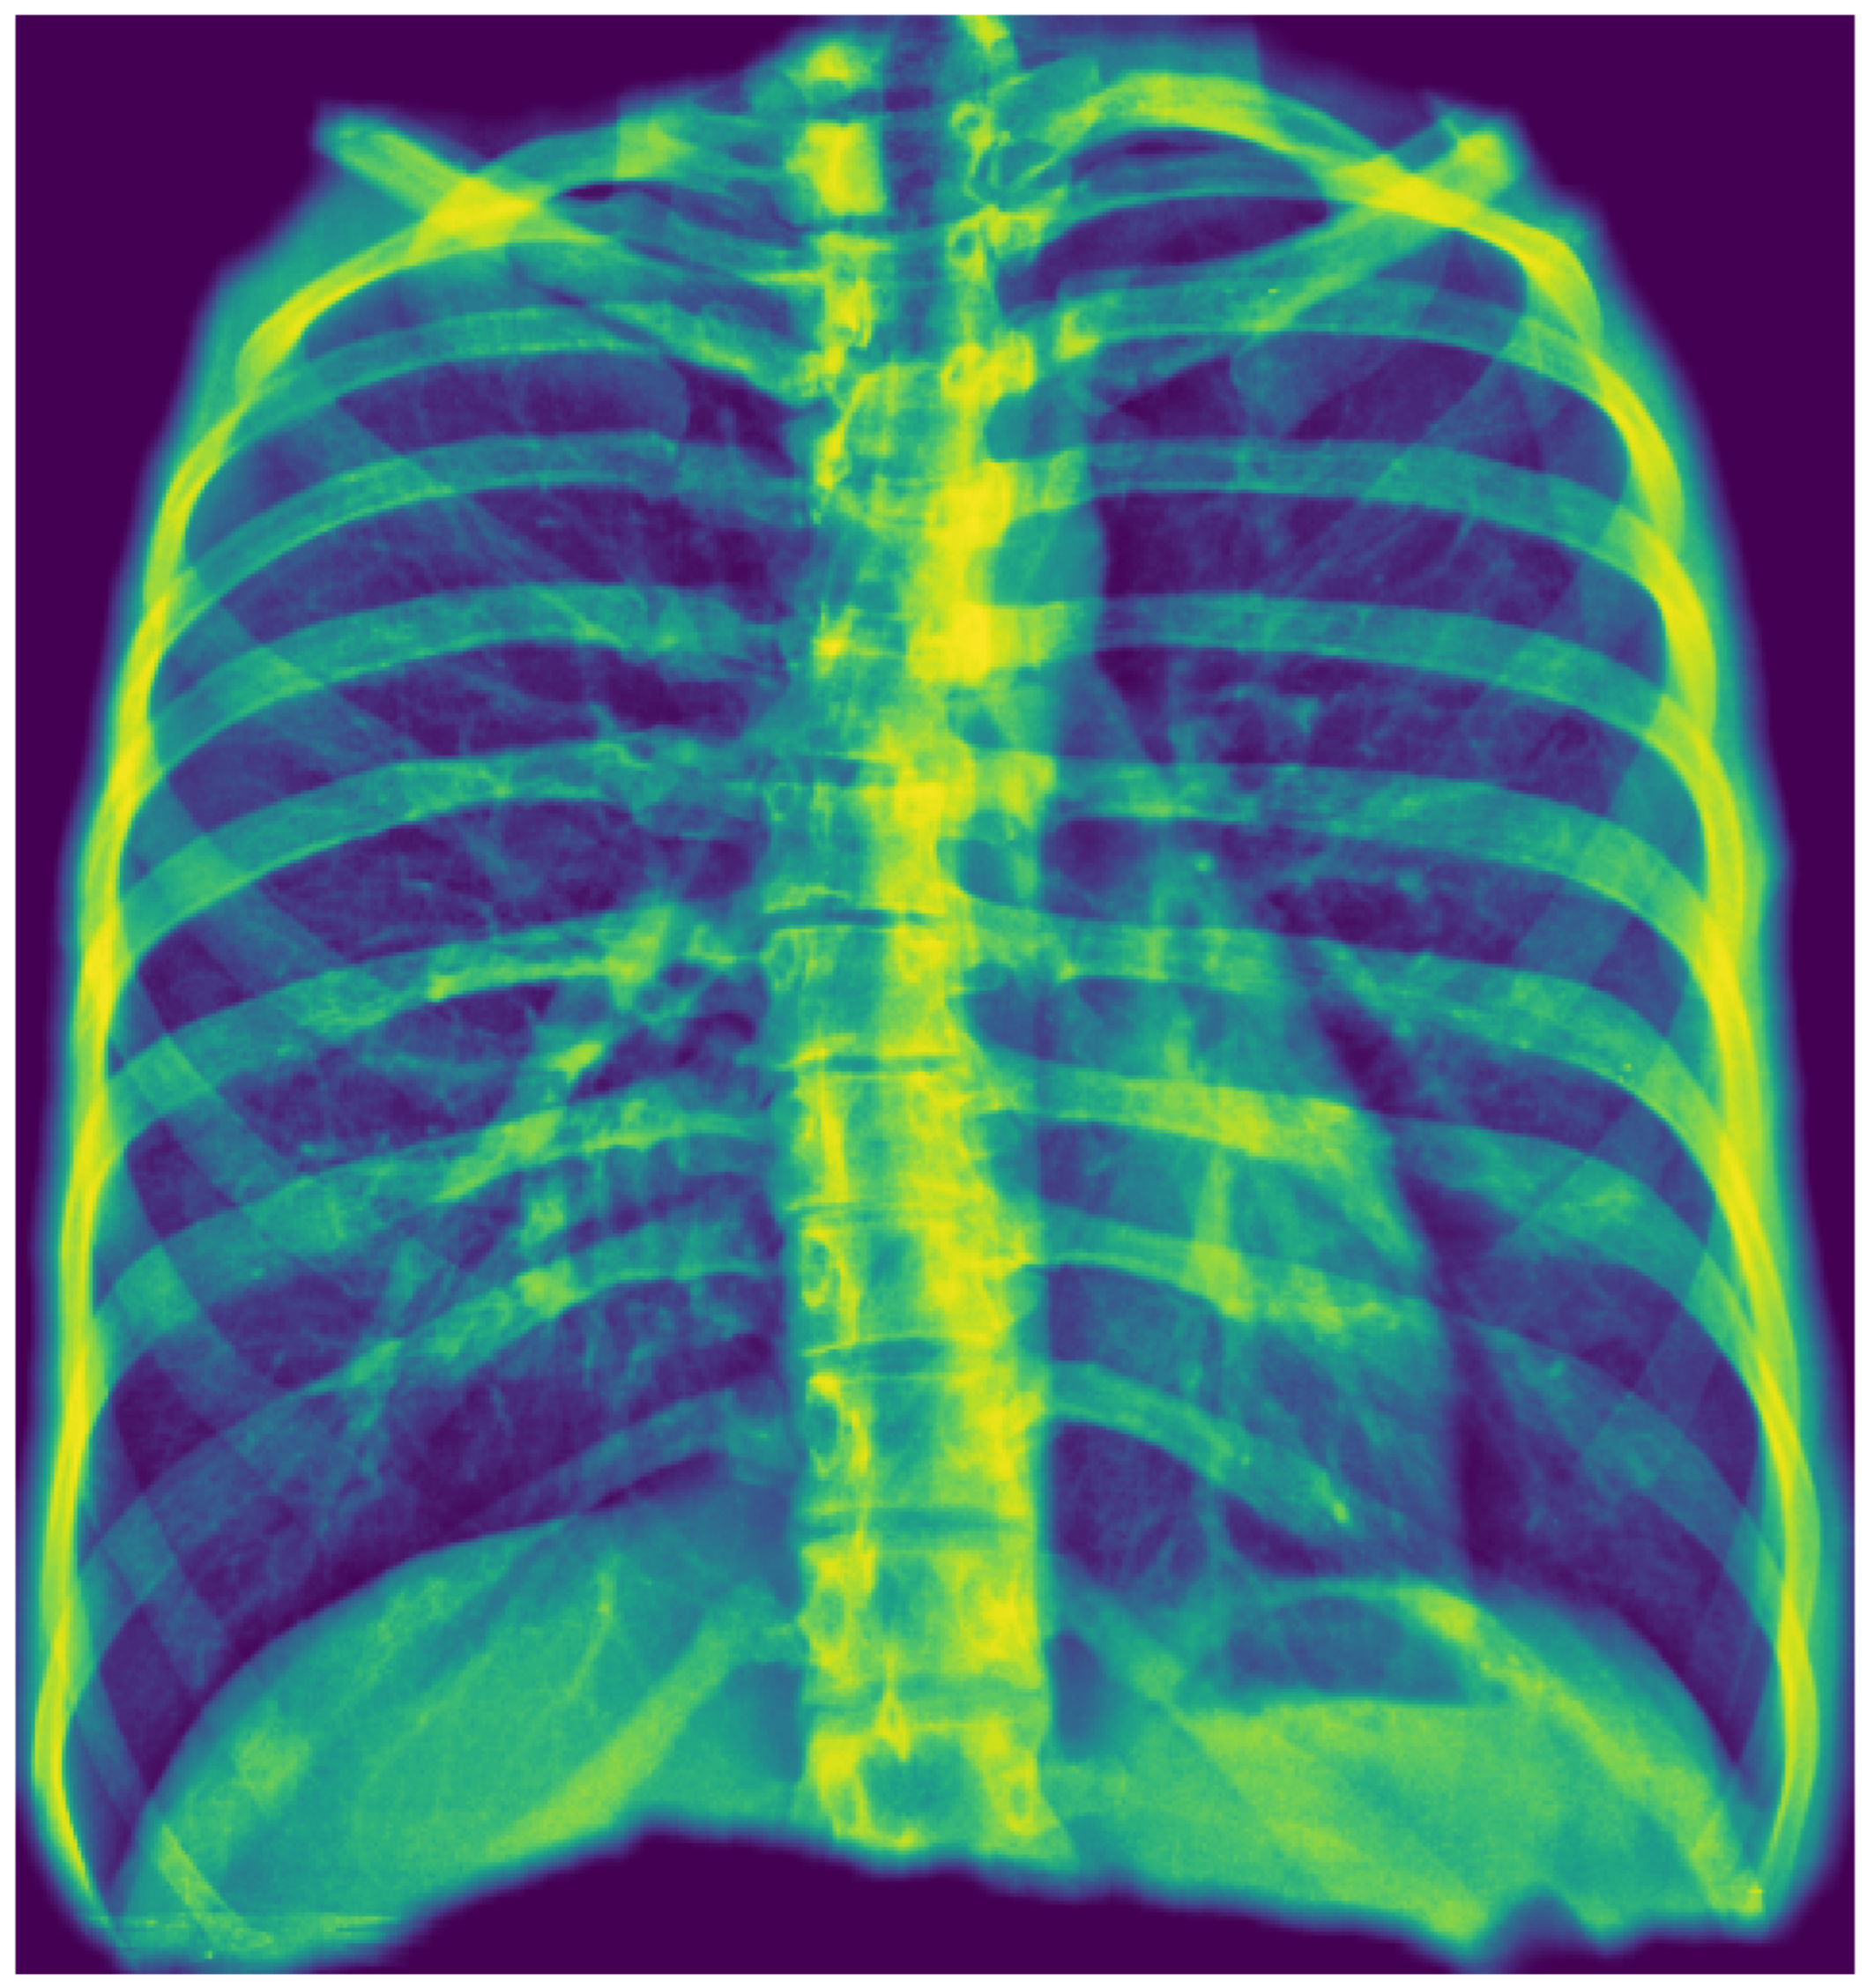

We employed a U-Net architecture with a MobileNetV2 backbone to segment the thoracic region and generate a unified “tongue-shaped” mask encompassing both lungs as well as the mediastinal and hilar regions. We chose U-Net for its proven effectiveness in medical image segmentation tasks, where high spatial precision is required. Its encoder–decoder “U” structure enabled the capture of both contextual and spatial information, facilitating the delineation of complex anatomical structures with high resolution. In this study, segmentation was used not only to isolate the relevant pulmonary region but also to constrain the subsequent classifier’s focus to clinically meaningful areas, thereby improving accuracy and reducing noise from irrelevant image regions.

We resized input images to 512 × 512 pixels and performed data augmentation using geometric and photometric transformations (padding, Gaussian noise, CLAHE, brightness/gamma adjustment, blur, motion blur, and hue/saturation shifts). The model was trained for 40 epochs with a batch size of 8 using the Adam optimizer (initial learning rate = 5 × 10−5) and a composite loss function combining Dice loss and binary focal loss to balance region overlap and class imbalance. Performance was monitored using Intersection over Union and F-score metrics, and the best model was selected by minimizing the validation loss with adaptive learning rate scheduling. Figure 2 illustrates the resulting mask, which ensures inclusion of central thoracic structures.

A key methodological strength of the underlying AI model is the use of a tongue-shaped segmentation mask. By including the mediastinum and hilar regions in the ROI, the model analyzes these diagnostically critical areas, which are often excluded by traditional lung-only segmentation. This approach creates a more clinically relevant area for analysis, which may improve the detection of central pathologies, especially those related to the cardiopulmonary system.

Figure 2. Example of first-stage segmentation: the generated “tongue-shaped” mask covering both lungs and mediastinal structures.